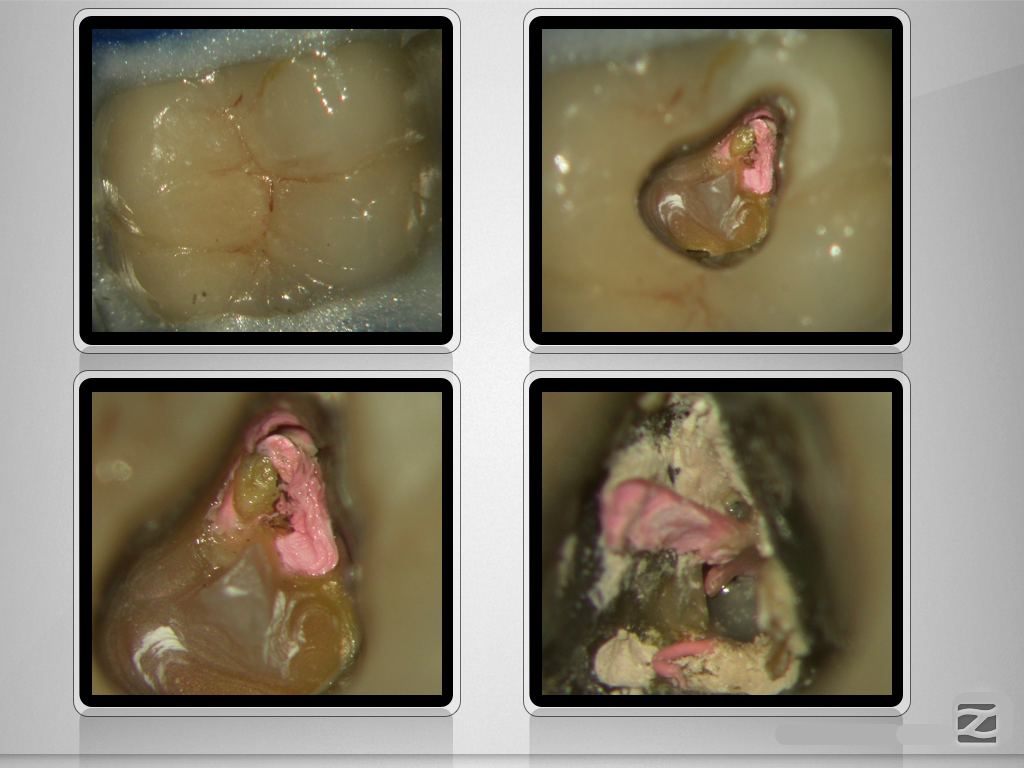

16D.002

Perforation und Krümmung